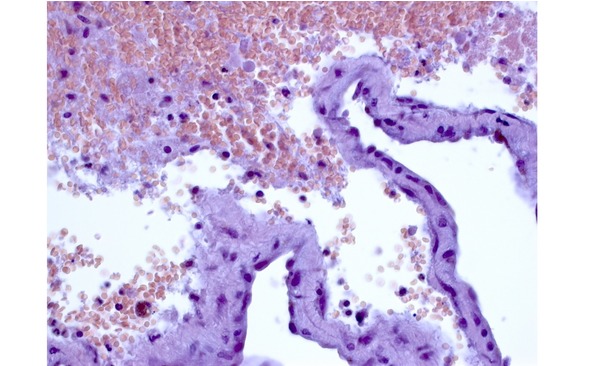

Рис. 17. Иммуногистохимическое исследование кавернозных мальформаций. А. Экспрессия гладкомышечного актина (HHF 35) в стенках сосудистых полостей КМ (коричневое рашивание). ув. х 400. Б. Экспрессия эндотелиального маркера CD31 в эндотелии и тромбах, облитерирурющих сосудистые полости (коричневое окрашивание) Ув. х 200. В. Экспрессия эндотелиального маркера CD34 в эндотелии, выстилающем сосудистые полости (коричневое окрашивание). Ув. х 400

Рис. 18. Экспрессия пролиферативного маркера Ki-67 в КМ (коричневое ядерное окрашивание, индекс 5%) в формирующейся капсуле гематомы. Ув. х 200

Рис. 19. Экспрессия VEGF в формирующемся тромбе (1) и в эндотелии (2) сосудистой полости КМ (коричневое окрашивание). Ув. х 400